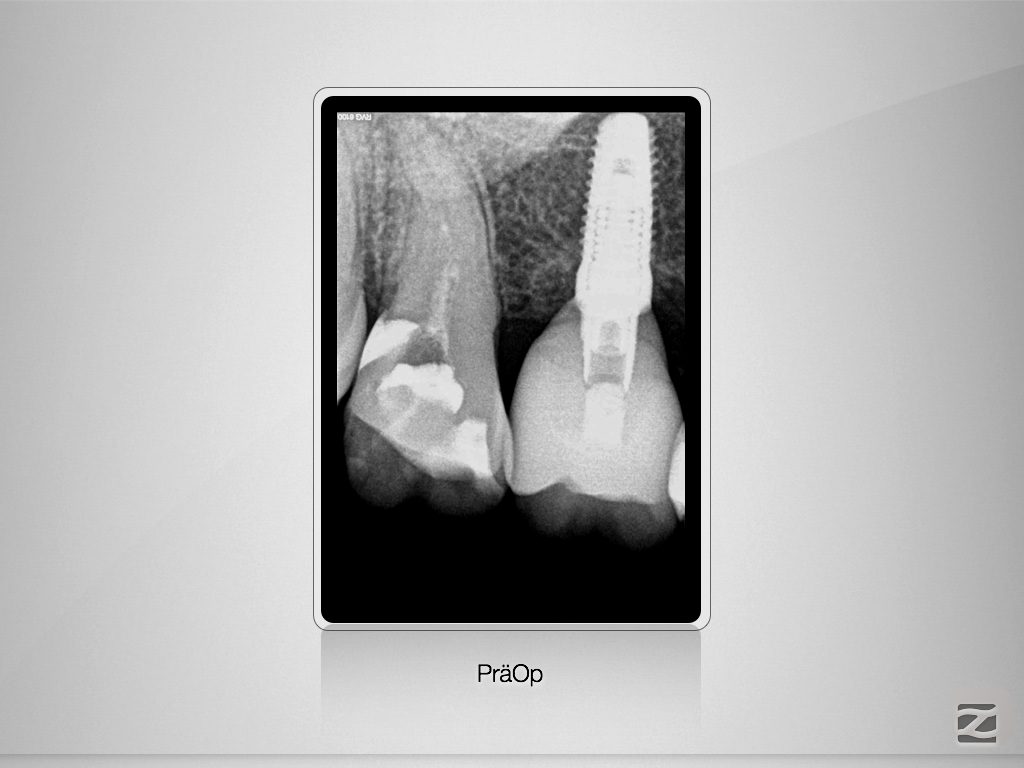

Gewusst, wo’s lang geht.